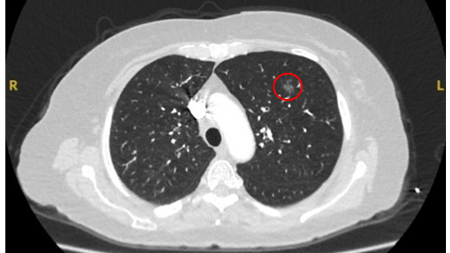

Computed tomography (CT) showing a small left upper lobe nodule with smooth margins, subsequently found to be a solitary colorectal metastasis on resection

From the collection of Dr George Tsaknis, MD, PhD, FRCP(London), MRQA, MAcadMEd, PGCert; used with permission